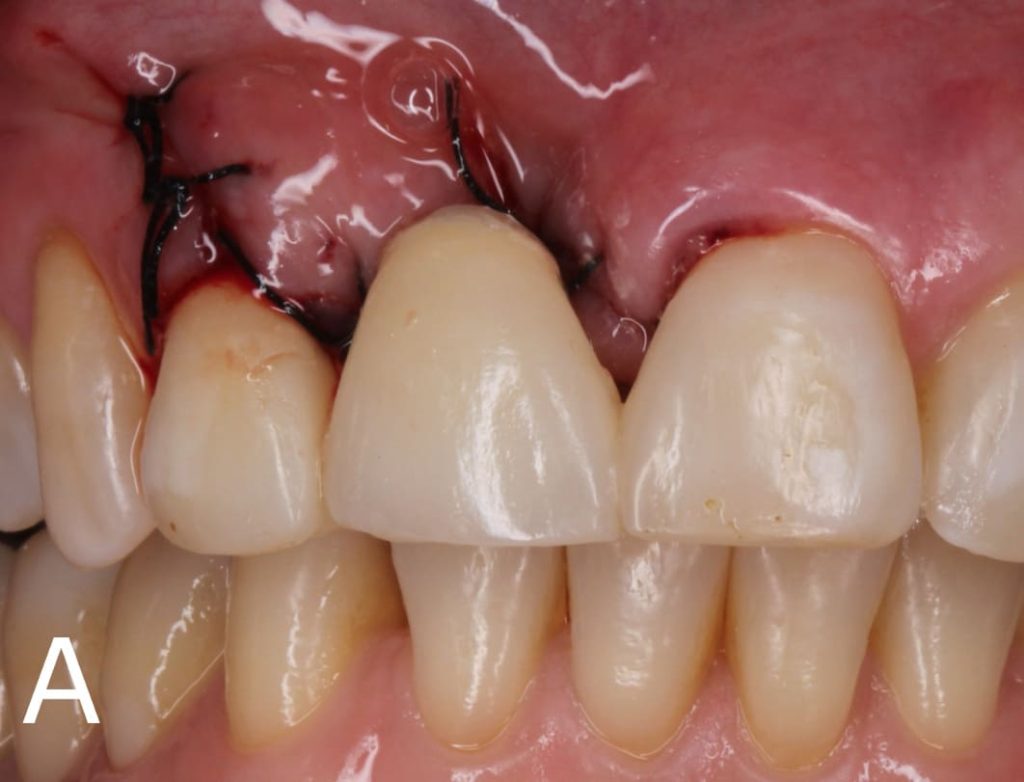

Se posicionó la fibra de vidrio en las preparaciones de los dientes 21 y 12 (Figura 5), se cubrió el área com resina y se fotopolimerizó por 20 segundos (Figura 6). Luego, el diente de stock se colocó sobre la fibra trenzada y se unió a ella con resina compuesta (Figura 7). Después de posicionar la confección de la prótesis adhesiva, se realizó el ajuste oclusal necesario respetando los fundamentos de una oclusión estable bilateral.

Incluso con indicación de carácter provisional, las prótesis adhesivas realizadas con fibra de vidrio trenzadas permiten la rehabilitación oral, en los casos en que se desea la máxima conservación de las estructuras dentarias, eliminando etapas laboratoriales, en los casos donde la reahabilitación con implantes está contraindicada.